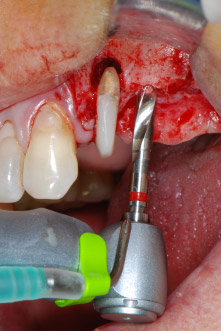

IImplant beds were prepared at sites 25 and 26 with rotary instruments, used in a contra-angle handpiece with a 20 : 1 transmission ratio with an updated powerful implant motor (Implantmed, W&H) (Fig. 8).

The implant bed was prepared with a new implant motor (Fig. 20), in combination with a contra-angle handpiece specifically designed for oral surgery and implantology.

The transmission rate of 20:1 together with the implant motor’s high torque of up to 6.2 Ncm allowed for slow speed preparation, implant insertion and thread cutting. Final preparation up to the sinus membrane was again performed with the piezoelectric unit and a round diamond instrument.